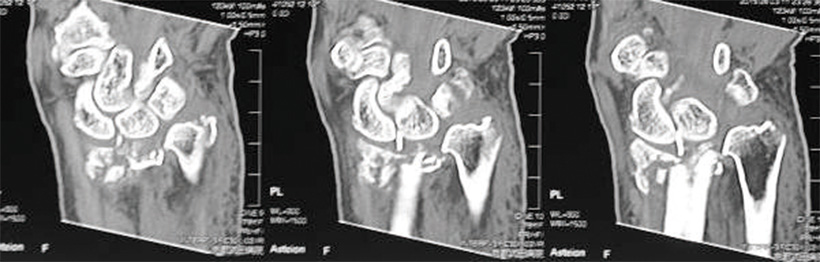

転落して受傷し来院されました。関節面が粉砕して大きくズレた骨折で、適切な位置で軟骨下骨を支持するのが難しいケースです。

ハイブリッドロッキングプレートを関節直下に固定しています。

1列目は強固に固定します。2列目は自由度があるため高い対応力を発揮します。

このCT画像のような粉砕骨折のケースでも、ハイブリッドロッキングプレートを用いた固定支持が可能です。